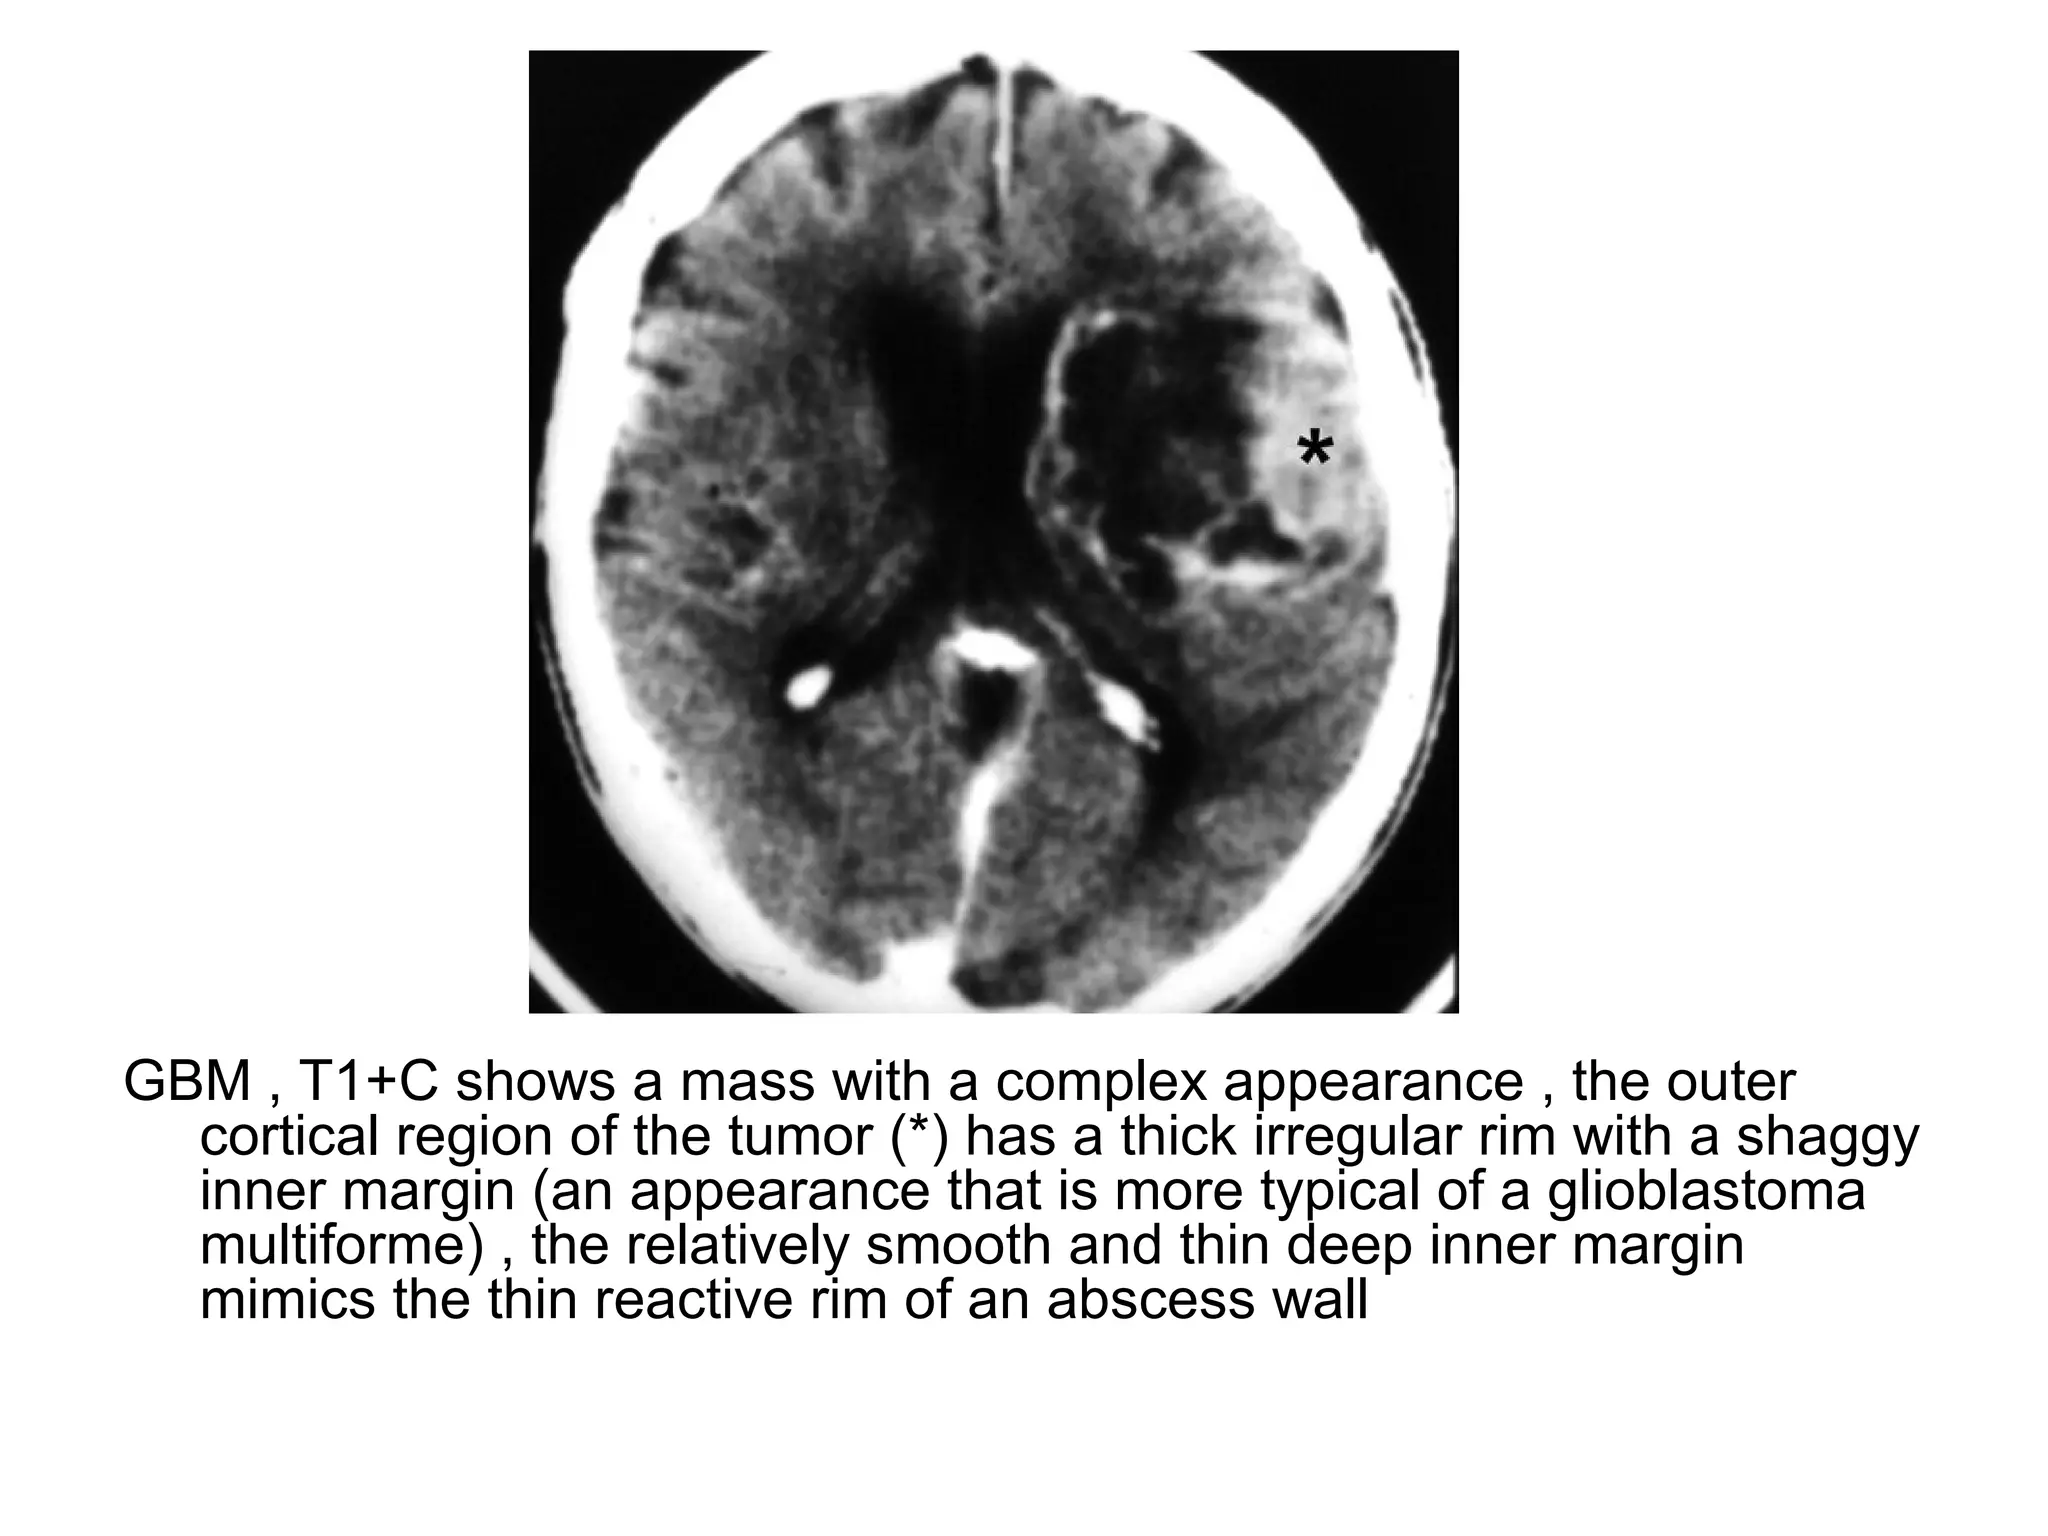

GBM , T1+C shows a mass with a complex appearance , the outer

cortical region of the tumor (*) has a thick irregular rim with a shaggy

inner margin (an appearance that is more typical of a glioblastoma

multiforme) , the relatively smooth and thin deep inner margin

mimics the thin reactive rim of an abscess wall

GBM , T1+Cshows a mass with a complex appearance , the outer cortical region of the tumor (*) has a thick irregular rim with a shaggy inner margin (an appearance that is more typical of a glioblastoma multiforme) , the relatively smooth and thin deep inner margin mimics the thin reactive rim of an abscess wall